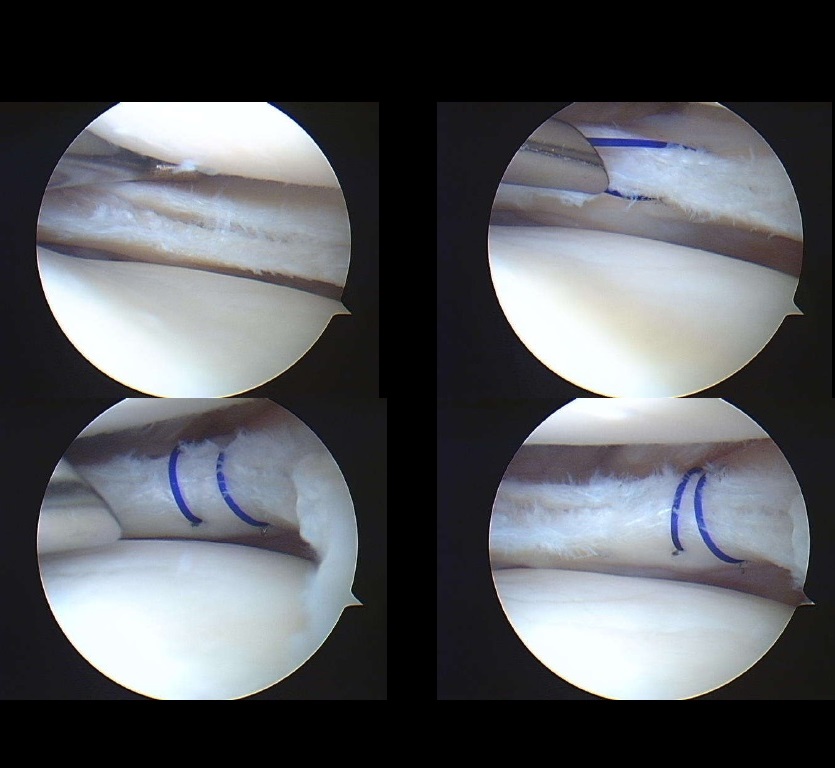

Outcome

Second-look arthroscopy performed months later demonstrated:

Complete healing of the repaired meniscus

Stable fixation with minimal visible sutures